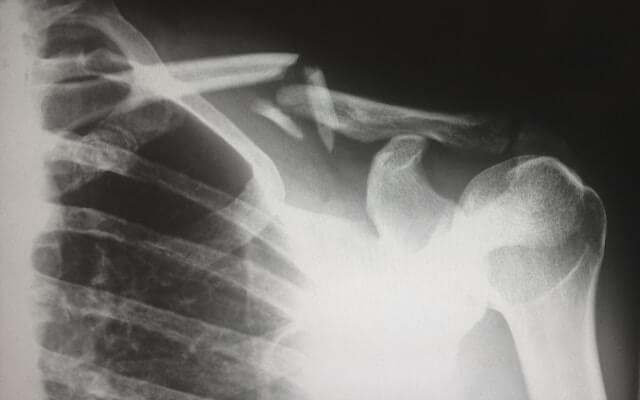

겨울철 눈이 오거나 빙판길이 있는 곳을 걷다가 미끄러질 경우 넘어지거나 엉덩방아를 찧게 될 수 있는데요. 이런 경우 건강한 성인이라면 고통보다 큰 부끄러움을 느끼고 서둘러 일어날 수도 있겠지만, 연세가 있어서 뼈가 약하시거나 특히 골다공증이 심한 환자분들 같은 경우에는 고관절 골절로 이어질 수 있습니다. 특히 고령의 골다공증 환자인 경우 이렇게 고관절 골절이 될 경우 회복이 되지 않아 심할 경우 사망에 이를 수 있습니다. 이번 시간에는 골다공증에 대해서 알아보도록 하겠습니다.

- 골절

골다공증의 가장 흔한 증상 중 하나로, 가벼운 충격이나 낙상으로도 쉽게 골절이 발생할 수 있습니다. 특히 손목, 척추, 엉덩이 골절이 흔합니다. - 통증